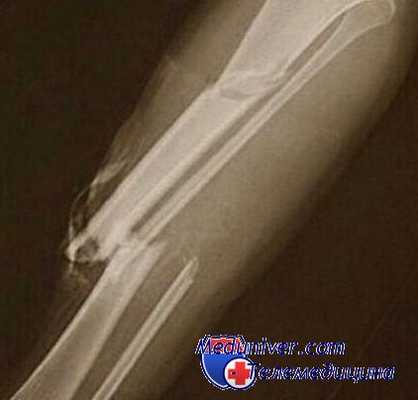

28. IX 1970 г. на гражданина Ж., 44 лет, совершил наезд автобус. В результате травмы возник поперечно-оскольчатыи перелом правого бедра, по поводу которого больному произведена операция интрамедуллярного металлоостеосинтеза. В послеоперационном периоде развился остеомиелит, а в дальнейшем — токсико-септическое состояние. Секвестерэктомия, а затем после генерализации процесса ампутация конечности не остановили септического процесса, и спустя 9 месяцев после травмы пострадавший скончался. При судебно-медицинском вскрытии подтвержден диагноз сепсиса и метастатической пневмонии и выявлен не распознанный ранее перелом одного ребра.